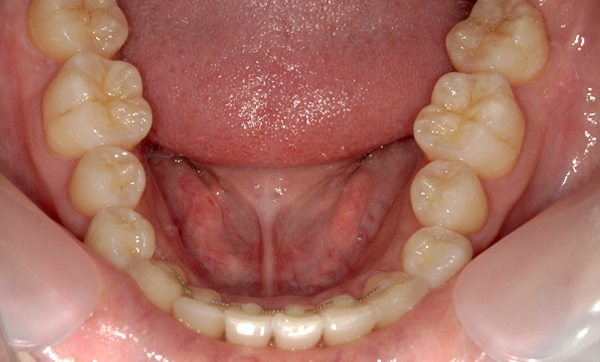

症例_009 「上下の前歯」症例

治療期間:7ヶ月金額:54万円+税20代女性捻転歯一部の反対咬合前歯のガタガタ